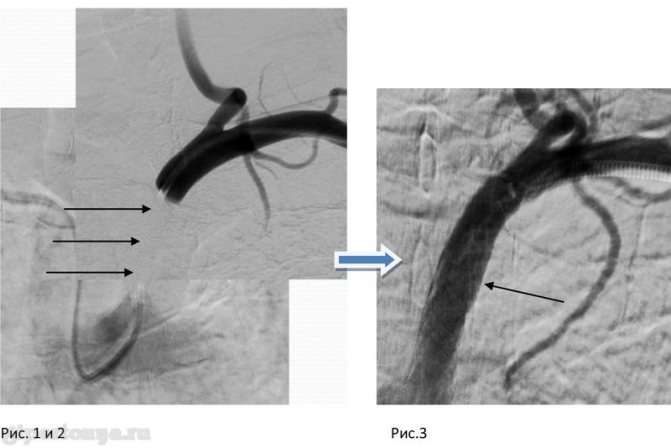

- В случае, если давление в ногах меньше, чем в руках (разница более 25-30%), то есть все основания подозревать у пациента коарктацию аорты. При этом заболевании просвет этого сосуда сегментарно суживается. Развитие патологии приводит к разрыву аорты и летальному исходу.

В последнем случае разница между величинами давления может достигать 20 мм рт. ст. Если систолическое давление на ногах ниже, чем на руках, то следует заподозрить обструктивное поражение аорты ниже места отхождения подключичных артерий или же стенозирование магистральных артерий нижних конечностей [76J.

б. Возникающие при компрессии бедра манжетой дискомфортные ощущения могут быть достаточно интенсивными и вызвать транзиторное повышение кровяного давления. В тех случаях, когда необходимо тщательное сравнение артериального давления на руках и ногах (например, у больных с подозрением на коарктацию аорты или аортальную регургитацию), соответствующие измерения должны осуществляться двумя наблюдателями одновременно.